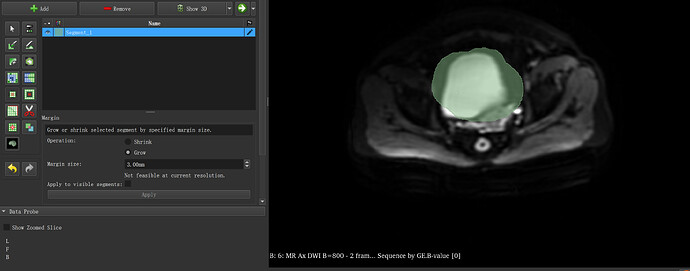

It says Not feasible at current resolution. You need to change your margin size to a value appropriate for the resolution of your dataset.

Thank you! My computer shows that the margin size needs to be set to 8mm

or more before the Apply button can be clicked.